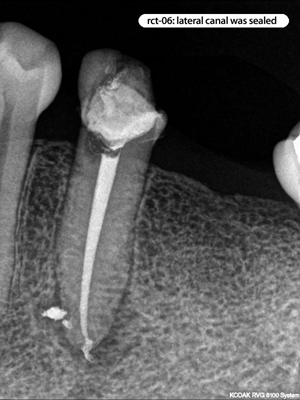

Root Canal Cases